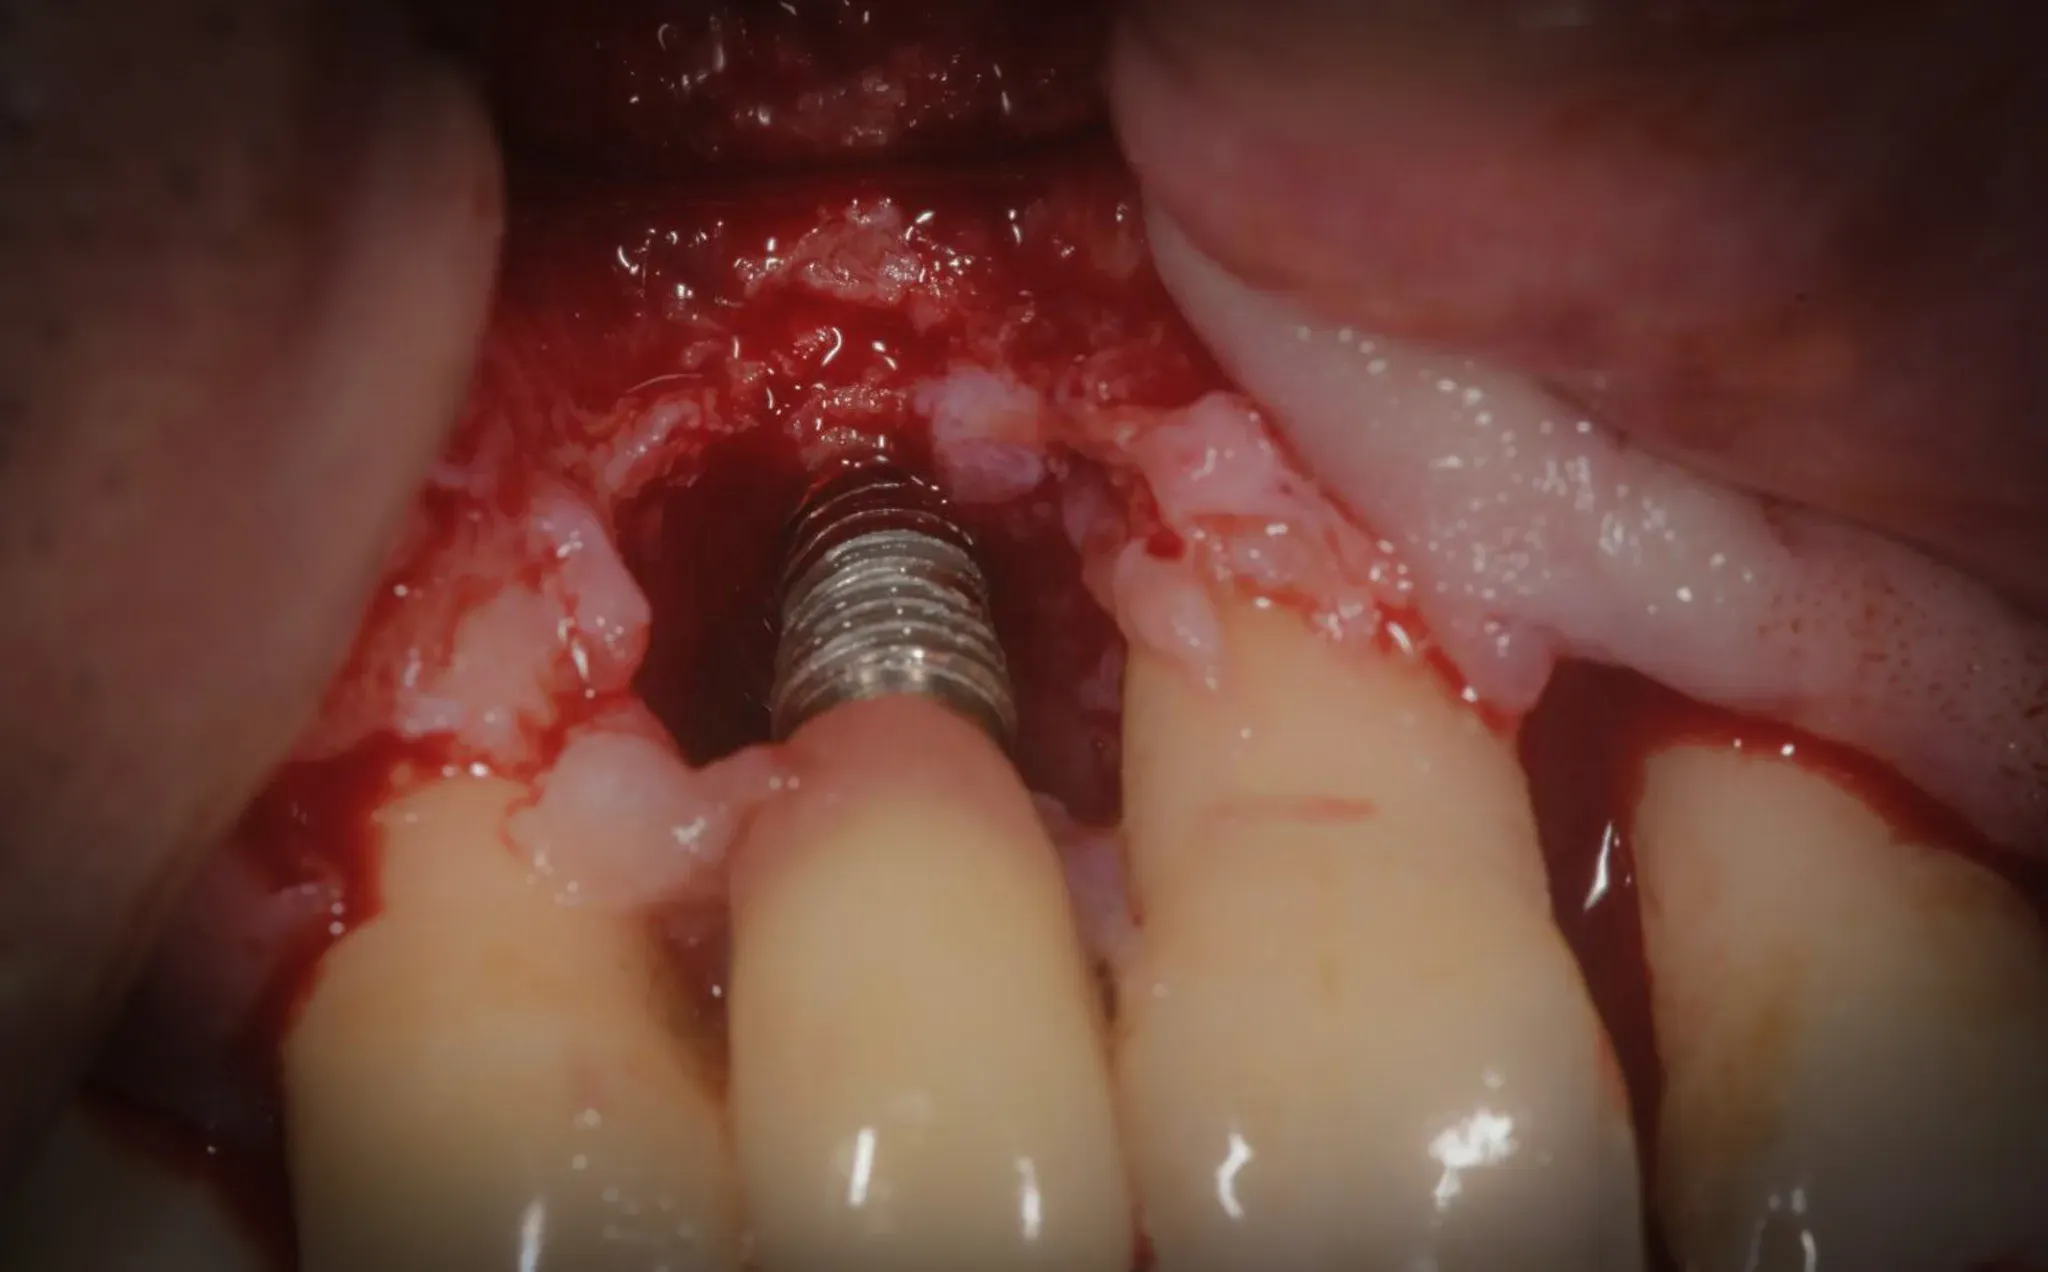

Full-thickness flap. The bone defect is exposed.

On the implant, the TST protocol is applied — the Ten Second Technique: HybenX for 10 seconds on the contaminated implant surface, followed by air polishing with sodium bicarbonate. The chemical reaction is visible to the naked eye: a white precipitate on the titanium surface, the protocol’s signature. The TST was published in Scientific Reports by De Nale et al. [1] — an in vitro study on failed explanted implants demonstrated through SEM and EDX that the technique effectively removes biofilm without altering the implant surface.